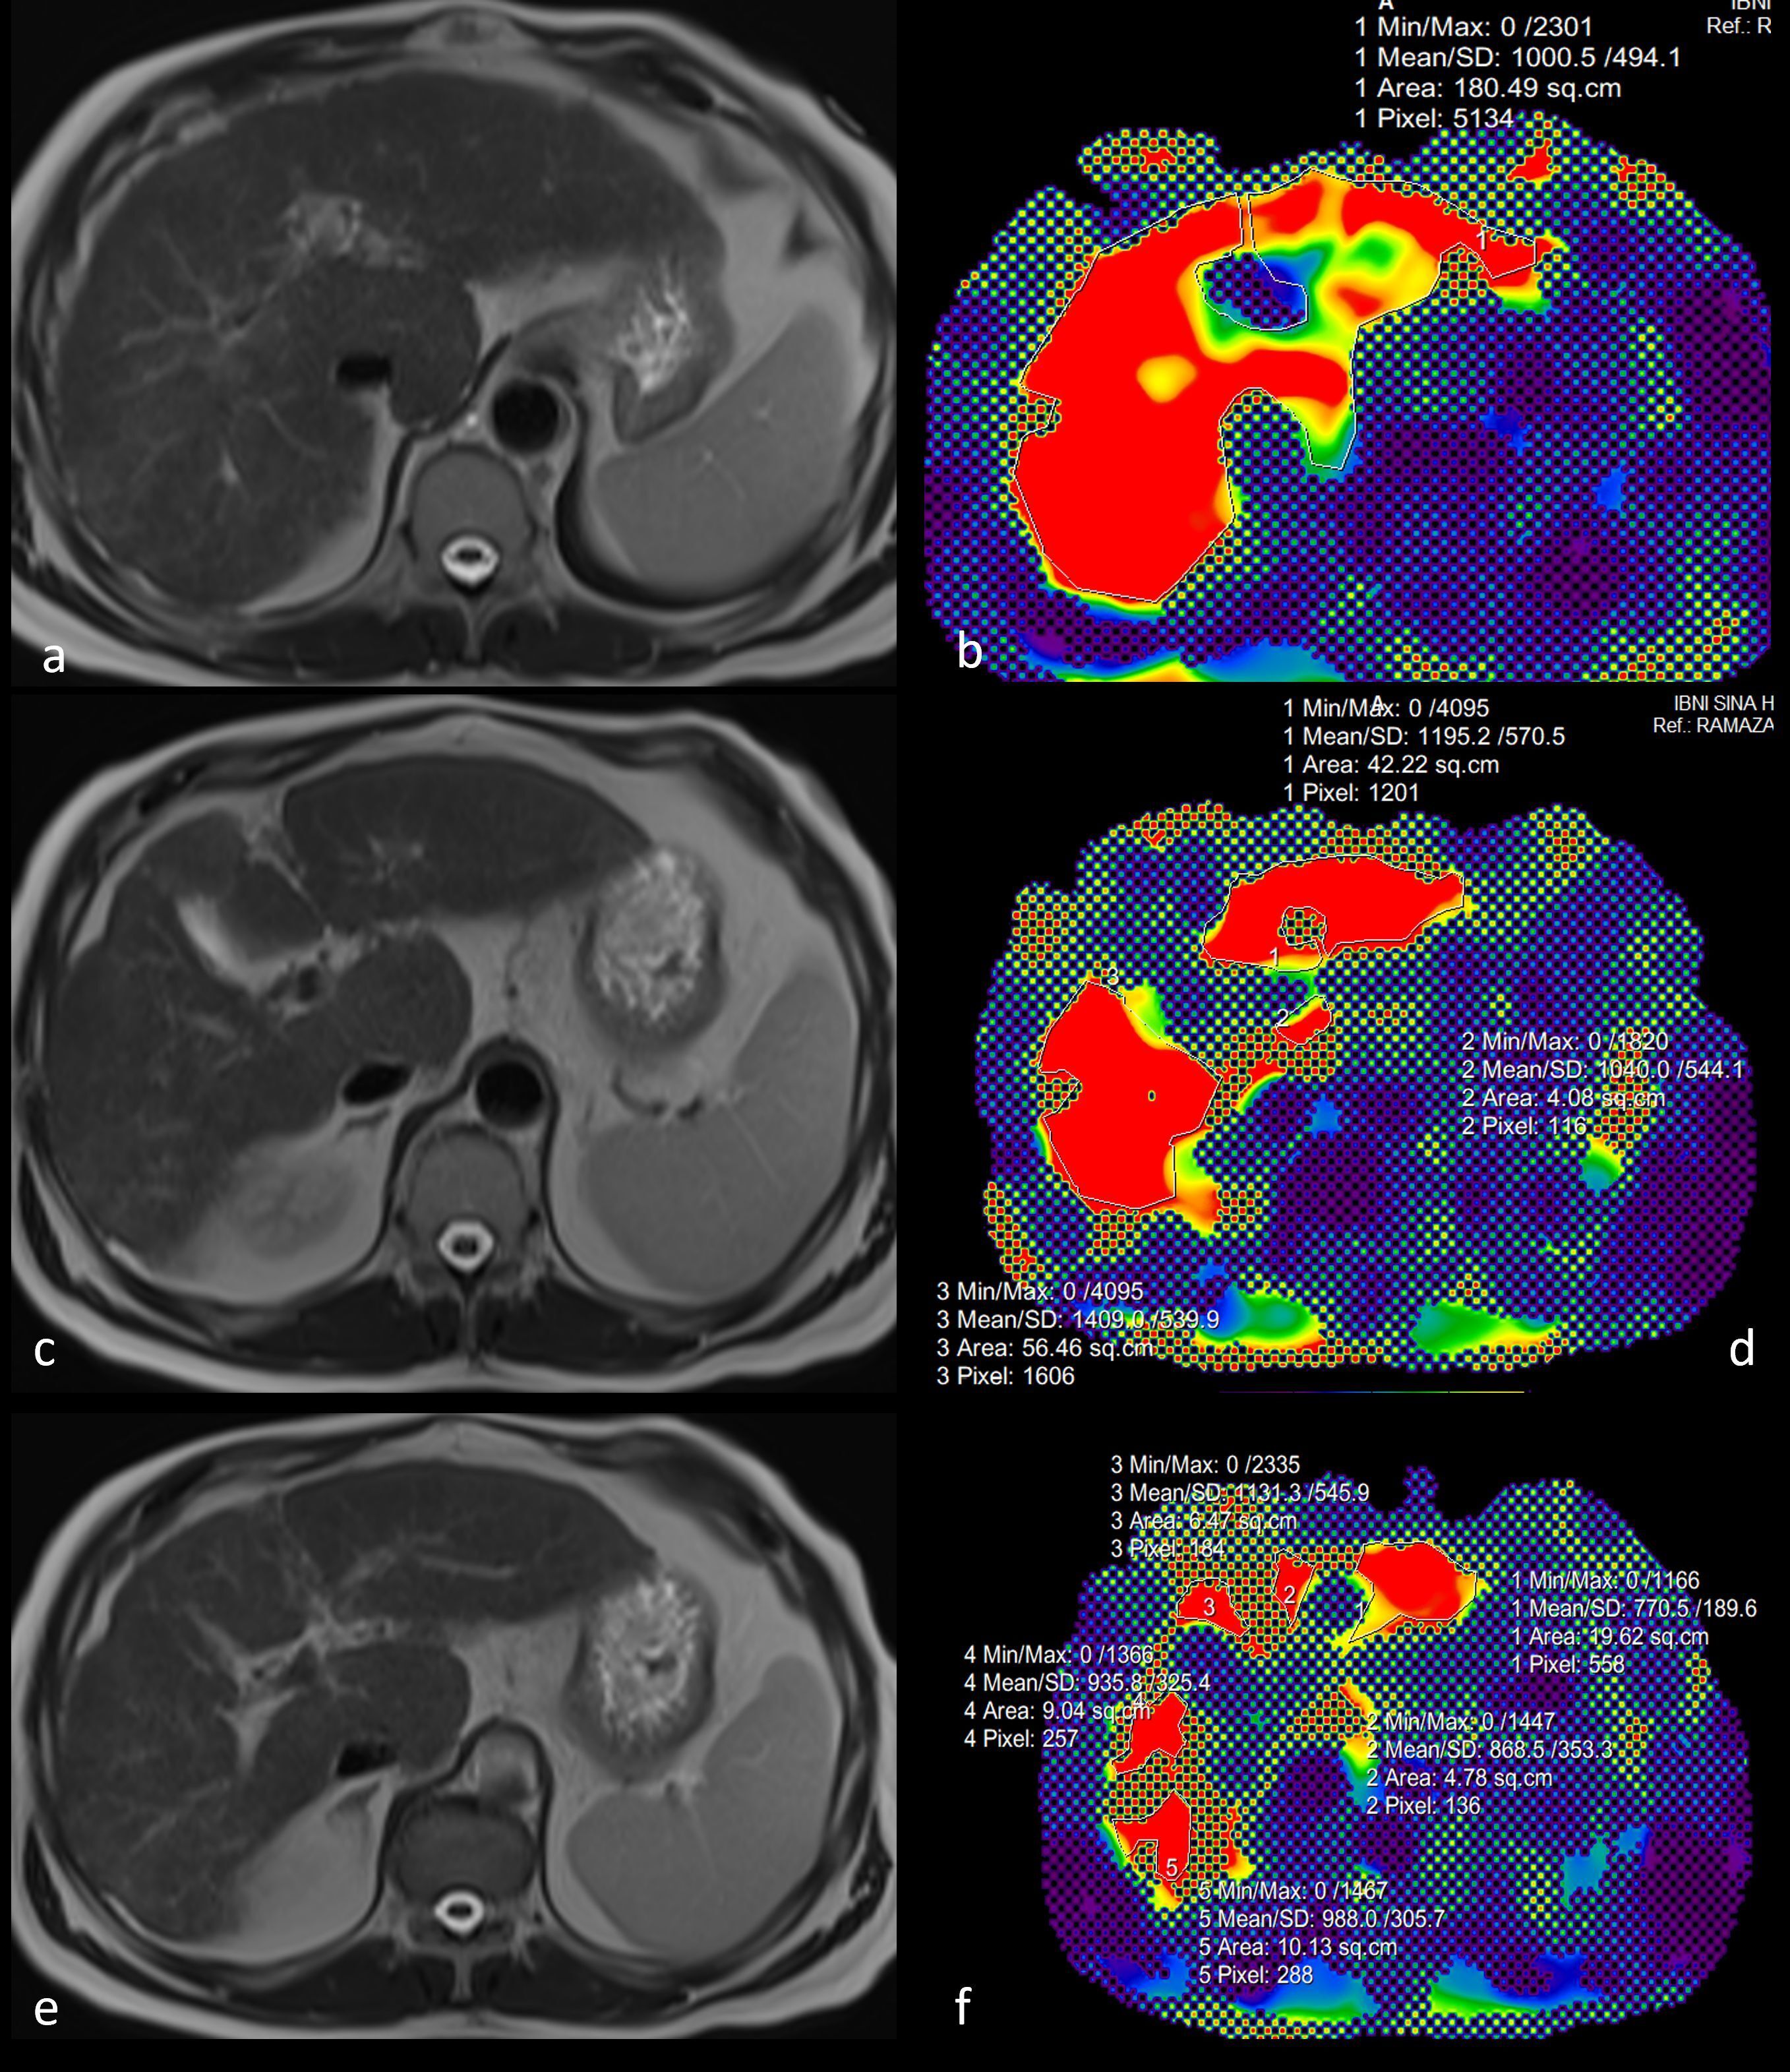

Interventional radiology

ORIGINAL PAPER

Transarterial chemoembolization with bleomycin and lipiodol: a novel treatment for giant hepatic haemangiomas

Pol J Radiol, 2025; 90: 465-470